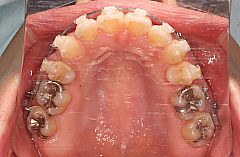

叢生治療例16(唇側矯正、表側矯正、歯科矯正用アンカースクリュー併用、抜歯)

主訴は前歯の凸凹(でこぼこ)です。前歯の凸凹のことを専門用語では叢生(そうせい)といいます。

この症例の場合、歯を並べるために不足しているスペースの量はそれほど多いわけではなく、歯を配列するだけであれば抜歯をせずに治療することも可能ですが、口唇の突出感も認められたため患者様と相談の上、抜歯をして矯正治療を行うことにしました。

この症例でも上下顎両側の第一小臼歯抜歯が候補として考えられますが、上顎左側の第二小臼歯と下顎右側の第二小臼歯にフルクラウン(補綴物)が装着されています。いずれも失活歯(神経が死んでいる歯)でした。

ただ、それを選択すると上下顎ともに左右非対称の抜歯部位となるため治療の難易度が上がり治療期間が長くなります。それで悩んだのですが患者様が歯科衛生士だったこともあり治療期間が長くなることと、左右非対称の力系を補正するために歯科矯正用アンカースクリュー(ミニインプラント)を使用することの了承を得ましたので上顎左側第二小臼歯(5番)、上顎右側第一小臼歯(4番)、下顎左側第一小臼歯(4番)、下顎右側第二小臼歯(5番)抜歯という上下顎左右で非対称な抜歯部位を選択して治療を開始しました。